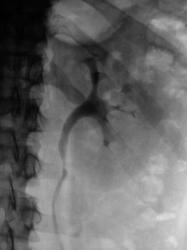

Почки контурируются в типичном месте, обычной формы и размеры. R-позитивных уроконкрементов в проекции мочевыносящих путей на обзорной урограмме не выявлено. ЧЛС контрастированы синхронно, не расширены. Мочеточники контрастированы, левый просматривается на всем протяжении, в нижней 1/3 незначительно стойко расширен, оттеснен кверху и вправо (хотя возможен такой вариант расположения устьев мочеточников - к сожалению правый мочеточник не визуализируется т.е. несчем сравнить). В мочевом пузыре, слева от срединной линии, дефект наполнения с четкой неровной границей.

Не хватает клинических данных (хотя бы укажите с какой стороны болит?) и других изображений контрастированного мочевого пузыря (необходимо выяснить стойкий это дефект наполнения или нет).

Валентин Львович! Дефект наполнения мочевого пузыря слева имеется. Сказать вне пузырный или внутрипузырный сложно. Я бы выполнил УЗИ мочевого пузыря. Урологам порекомендовал бы цистоскопию.

Согласен с последним постом; думаю после УЗИ мочевого пузыря вопросов будет меньше( вообще, в данной клинической ситуации оптимальнее было бы начать с УЗИ мочевыводящей системы).